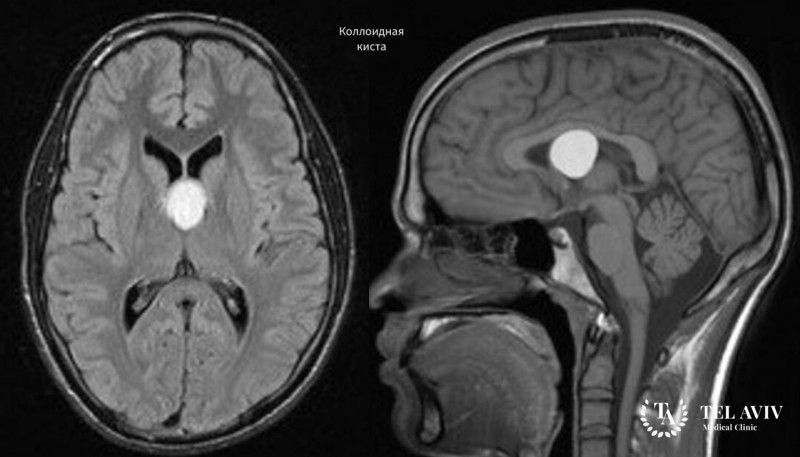

Кисты в головном мозге относят к группе доброкачественных образований. Они формируются из жидкости, элементов мягкой ткани. Для кисты не характерно […]